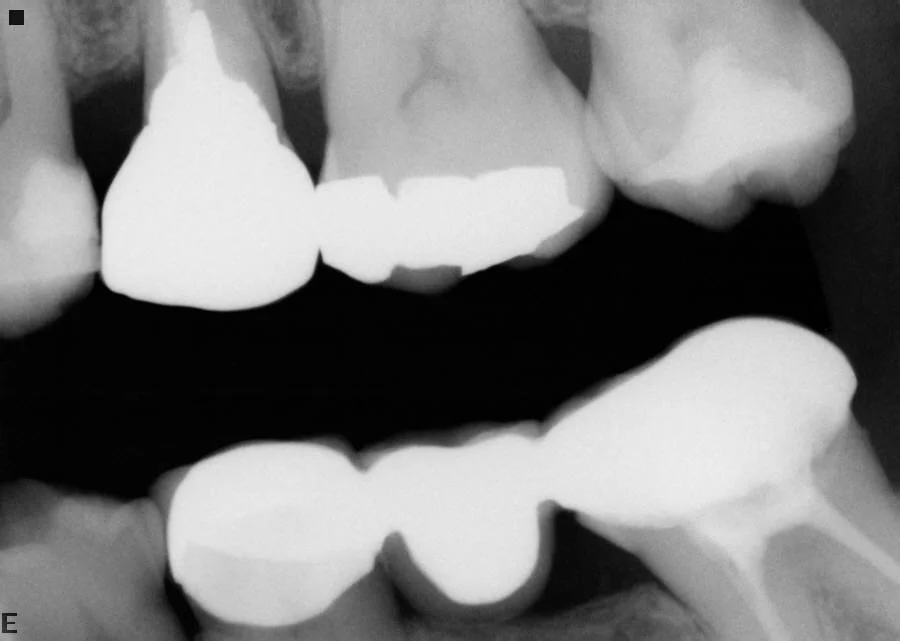

Restorations: RCT+Emax crowns

Before